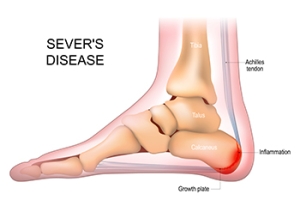

What Is Sever’s Disease?

Sever’s disease is a frequent cause of heel pain in children going through their growth spurt, typically between the ages of eight and 14. This condition arises when the Achilles tendon, which links the calf muscle to the heel, grows slower than the bones in the feet. As a result, the tendon pulls on the heel, causing discomfort. Symptoms can include heel pain during or after physical activity, limping, and walking on tiptoes. Though Sever’s disease often improves as growth slows, there are effective methods that can manage the pain. Adjusting activity levels, taking medications, and using orthotics can provide relief. If your child is struggling with heel pain, it is suggested you schedule an appointment with a podiatrist who can offer a proper diagnosis and recommend the best course of action to ensure your child’s comfort and continued activity.

Sever's disease often occurs in children and teens. If your child is experiencing foot or ankle pain, see Lance Greiff, DPM from Great Neck Podiatry. Our doctor can treat your child’s foot and ankle needs.

Sever’s Disease

Sever’s disease is also known as calcaneal apophysitis, which is a medical condition that causes heel pain I none or both feet. The disease is known to affect children between the ages of 8 and 14.

Sever’s disease occurs when part of the child’s heel known as the growth plate (calcaneal epiphysis) is attached to the Achilles tendon. This area can suffer injury when the muscles and tendons of the growing foot do not keep pace with bone growth. Therefore, the constant pain which one experiences at the back of the heel will make the child unable to put any weight on the heel. The child is then forced to walk on their toes.

Symptoms

Acute pain – Pain associated with Sever’s disease is usually felt in the heel when the child engages in physical activity such as walking, jumping and or running.

Highly active – Children who are very active are among the most susceptible in experiencing Sever’s disease, because of the stress and tension placed on their feet.

Sever's Disease

Sever's disease, also known as calcaneal apophysitis, is a medical condition that causes heel pain in children’s feet while they’re growing. Sever's disease occurs most commonly in boys and girls between the ages of 8 and 14.

Sever's disease occurs when the child’s growth plate, or the calcaneal epiphysis, an area attached to the Achilles tendon, is injured or when the muscles and tendons of the growing foot do not keep pace with bone growth. The result is constant pain experienced at the back of the heel and the inability to put any weight on the heel. This forces the child to bear weight on their toes while walking. When a toe gait develops, the child must change the way they walk to avoid placing weight on the painful heel. If this is not properly addressed, this can lead to further developmental problems.

The most common symptom of Sever's disease is acute pain felt in the heel when a child engages in physical activity such as walking, jumping or running. Children who are active athletes are among the group most susceptible to experiencing Sever's disease. This is due to the extreme stress and tension placed on their growing feet. The rolling movement of the foot during walking or running and obesity are both additional conditions linked to causing Sever's disease.

The first step in treating Sever's disease is to rest the foot and leg and avoid physical activity. Over the counter pain-relieving and anti-inflammatory medications can be helpful for reducing the amount of heel pain. A child with Sever's disease should also wear shoes that properly support the heel and the arch of the foot. Consider purchasing orthotic shoe inserts which can help support the heel and foot while it is healing. Most patients with Sever's disease symptoms report an eventual elimination of heel pain after wearing orthotic insoles that support the affected heel.

Sever's disease may affect either one heel or both. It is important for a child experiencing heel pain to be examined by a foot doctor who can apply the squeeze test. The squeeze test compresses both sides of the heel in order to determine if there is intense pain. Discourage any child diagnosed with Sever's disease from going barefoot as this can intensify the problem. Apply ice packs to the affected painful heel two or three times a day for pain relief.

Exercises that help stretch the calf muscles and hamstrings are effective at treating Sever's disease. An exercise known as foot curling has also proven to be very effective at treating Sever's disease. When foot curling, the foot is pointed away from the body, then curled toward the body to help stretch the muscles. The curling exercise should be done in sets of 10 or 20 repetitions and repeated several times throughout the day.

Treatment methods can continue for at least 2 weeks and as long as 2 months before the heel pain completely disappears. A child can continue doing daily stretching exercises for the legs and feet to prevent Sever’s disease from returning.